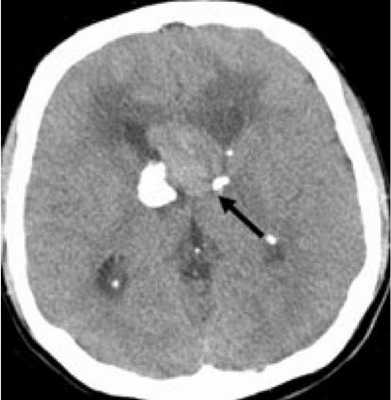

Наиболее типичными нарушениями в головном мозге являются корковые туберсы и субэпендимарные узлы. Туберсы могут быть как единичными, так и множественными, располагаются в виде выступов над единичной или прилегающими бороздами коры, расширяя их. Субэпендимарные узлы локализуются в стенках боковых желудочков и, реже, в стенках III и IV желудочков мозга. У новорожденных субэпендимарные узлы редко бывают кальцифицированными. По мере роста ребенка наблюдается постепенное отложение кальция в субэпендимарных узлах.

Субэпендимарные узлы в 10% случаев трансформируются в гиганто-клеточную астроцитому, которые манифестируют обычно между 5 и 10 годами жизни, имеют тенденцию к росту и локализуются у отверстия Монро

Субэпендимарные кальцификаты и корковые туберсы на КТ головного мозга ребенка с туберозным склерозом

КТ головного мозга при туберозном склерозе. Видны кальцинированные субэпендимальные узелки в стенках боковых желудочков.